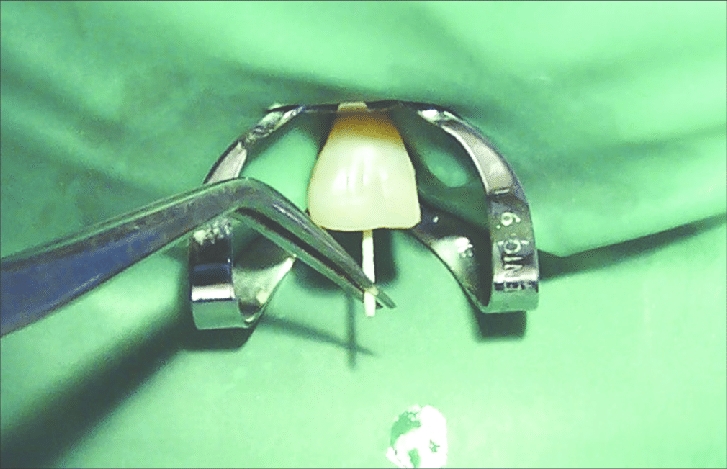

Endodontics: Gutta Percha & Paper Points.

Temporary Restoratives: DiaTemp, DiaTemp Flow, eTemp Irrigations & Instruments, Dia-Prep Pro (EDTA), Disposable Endo Irrigation Tips, Diaflex Irrigaion Syringe, Sterilized Irrigation Tips (Side-Open Type), Dia-Kondensor.